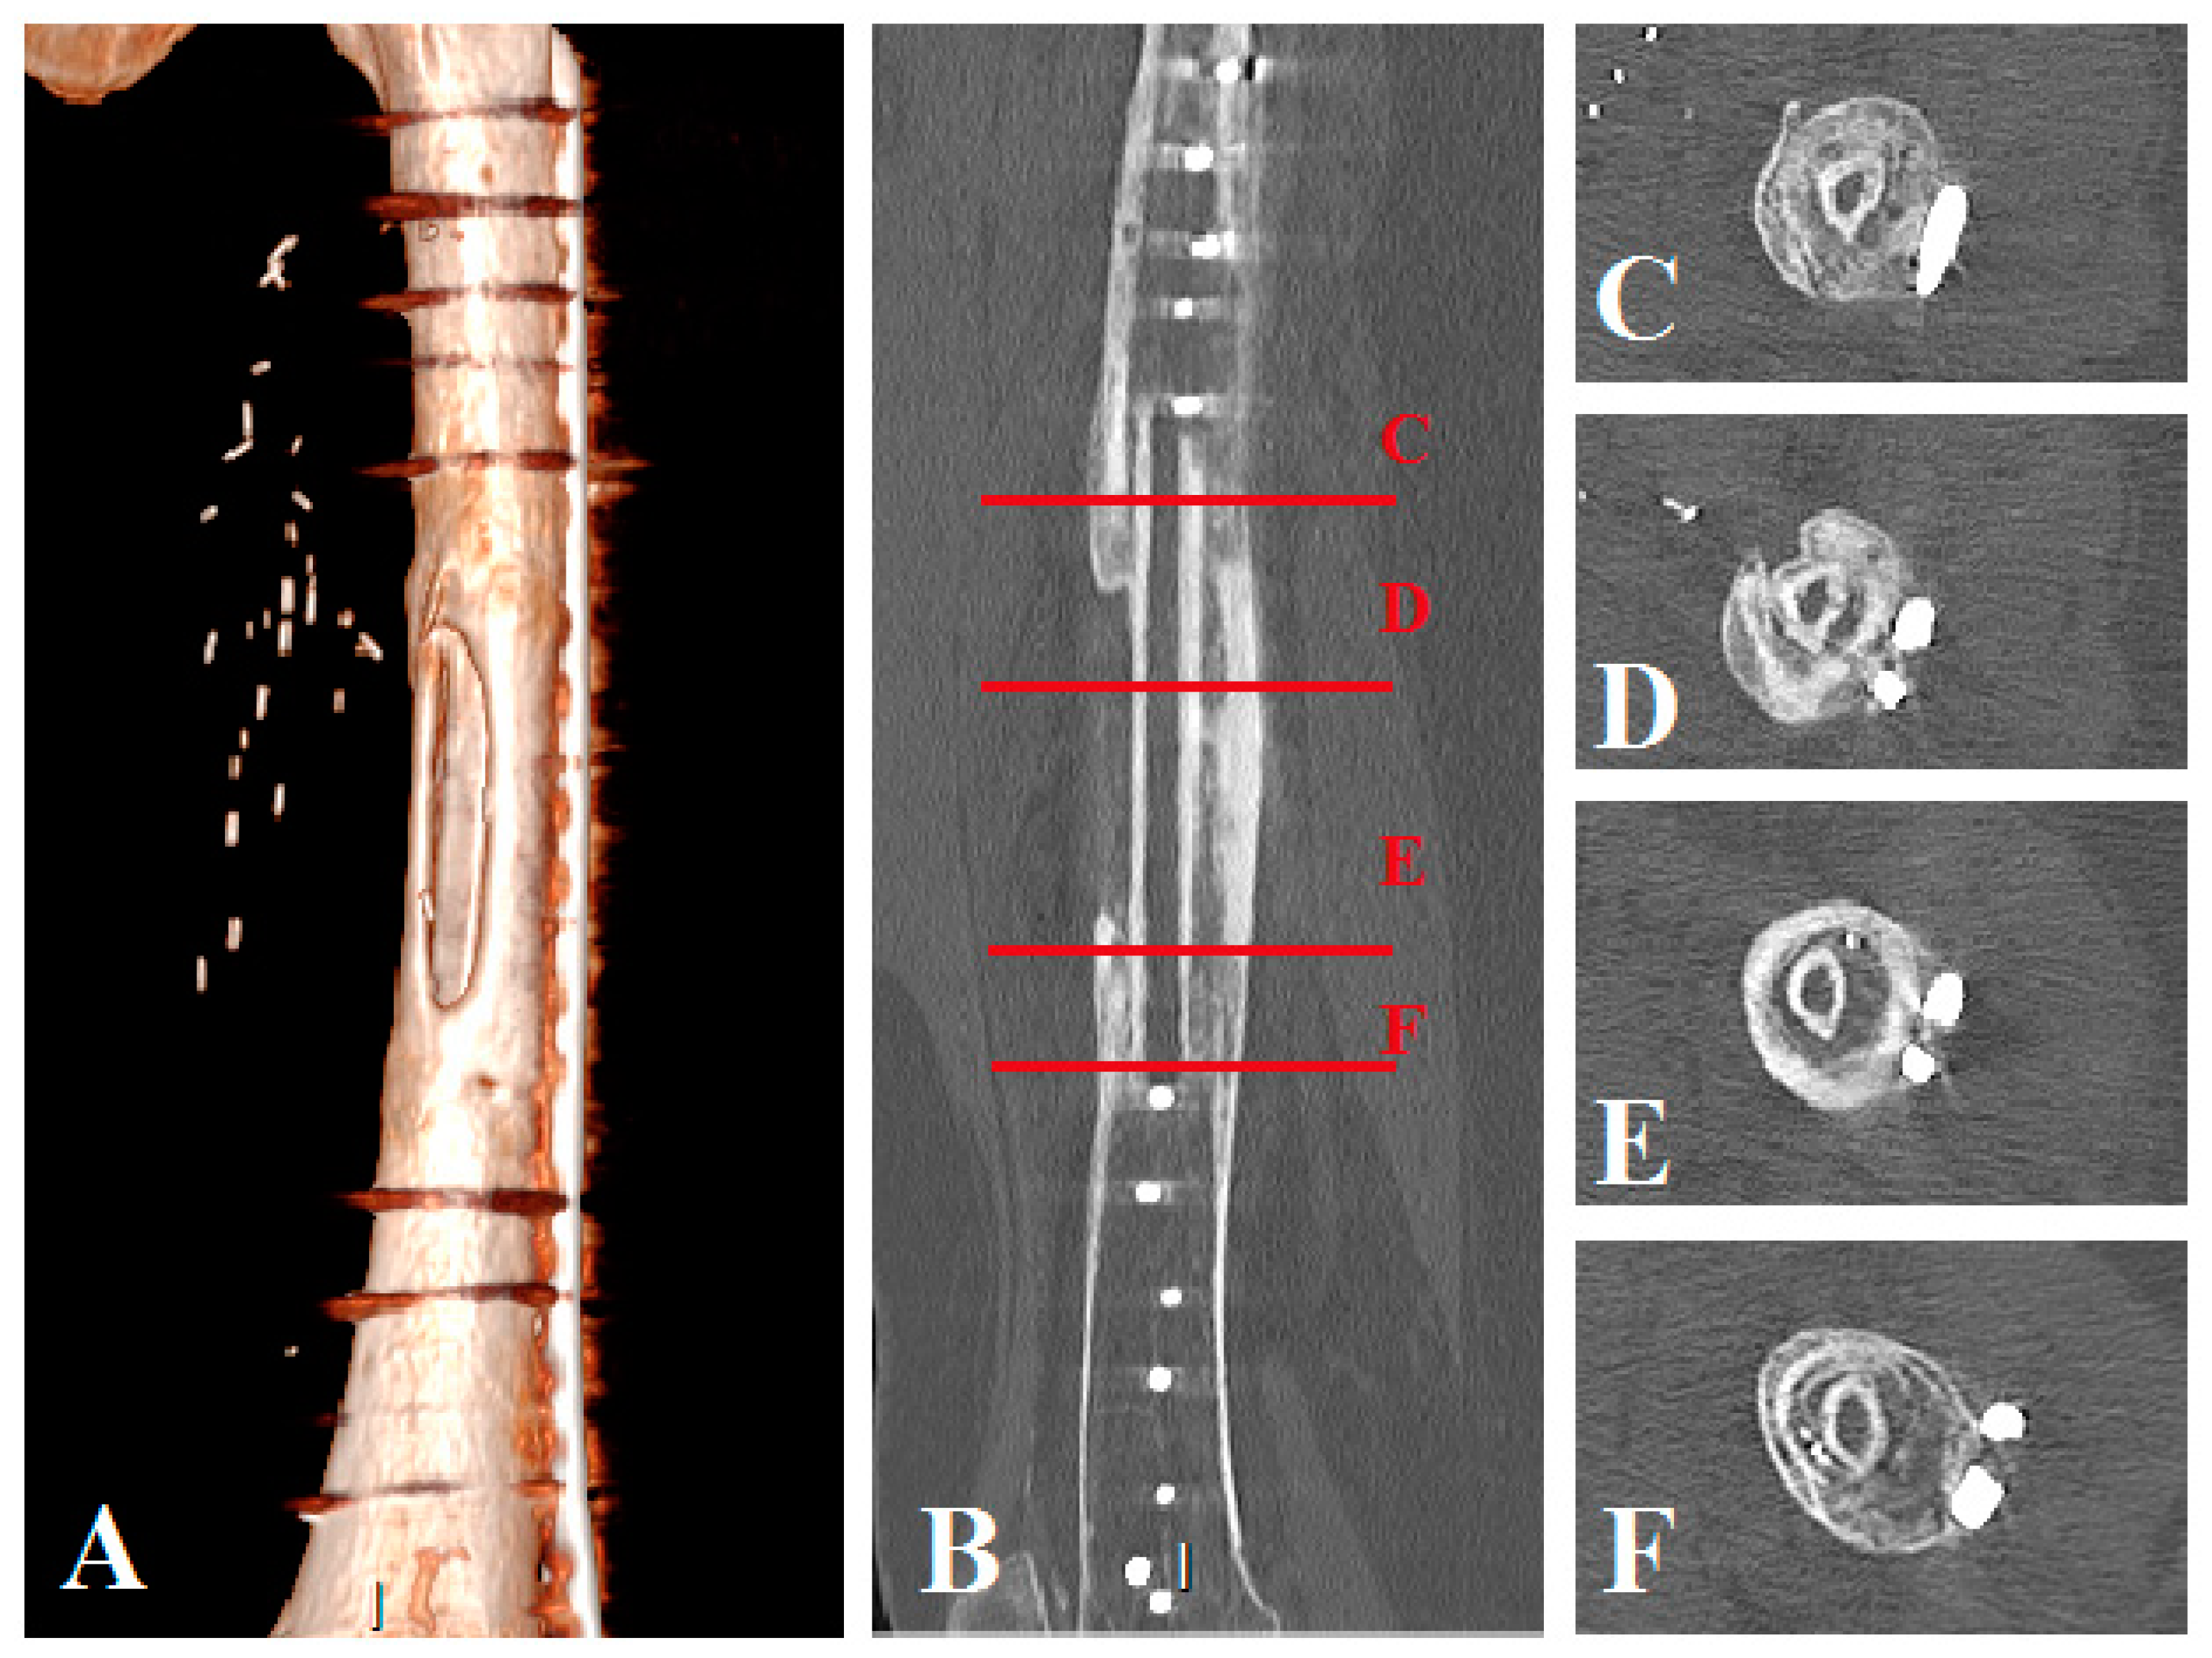

Figure 5.

Patient No. 1 CT scan control at 14 months postoperatively: (A) CT scan 3D reconstruction of the healed allograft; (B) sagittal plane view with axial view level representation: (C–F) (C) axial view of the proximal host femur with the healed fibula graft, (D,E) axial views of the healed fibula graft in the allograft, (F) axial view of the distal host femur with the healed fibula graft.